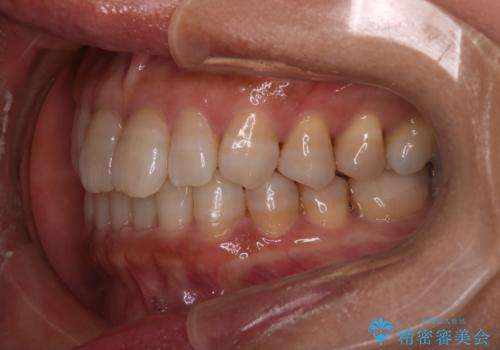

【インビザライン】下前歯だけを治したい

- 50代女性

- 矯正装置

- インビザライン

- 治療期間

- 8ヶ月

- 下前歯のがたつきにより唇を巻き込んでかんでしまい痛いため矯正をしたいという主訴で来院されました。今回は下顎前歯のみという強い希望があり、下顎のみのインビザライン矯正をしました。

叢生を改善するためのスペースはIPRと拡大を行いました。治療後は唇を巻き込んでしまう主訴が改善し、ご満足していただけました。